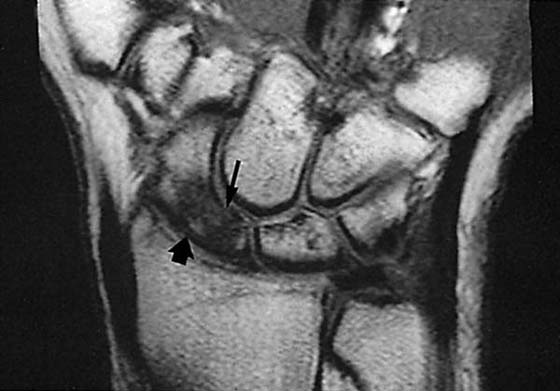

MRI is of great value in defining soft tissue abnormalities (Figs. 13-17 to 13-19, all online). In the evaluation of tumors, it cannot provide a specific diagnosis, but it can define the size of the lesion and the extent of involvement of marrow and neurovascular structures (Fig. 13-20, online).27 Other soft tissue abnormalities diagnosed more easily by MRI include ganglions, ligament tears, and cartilage abnormalities (Fig. 13-21).28,29 Dorsal wrist pain can be attributed to hypertrophy of the dorsal capsule as well as ganglions that may be occult and not palpable. Patients with dorsal wrist pain of unknown origin are therefore candidates for MRI evaluation. MRI is especially helpful in diagnosing tears of the scapholunate and lunotriquetral ligaments, particularly when dissociation of the scapholunate is not evident on plain films.30 Excellent depiction of the TFC can be achieved with MRI, but the image must be interpreted carefully; thinning of the disk occurs in many patients, but a tear of this structure is not diagnosed unless an avulsion from the ulnar or radial insertion can be observed.31-33

The carpal ligaments are best visualized on thin-section 3D gradient recalled echo (GRE) MR sequences in the coronal and axial planes. They appear as signal voids bridging the carpal bones. Ligament strains can be diagnosed if the signal is abnormal or the structure is attenuated. Discontinuity, complete absence, and increased intercarpal distances are findings compatible with ligament tears. The best finding for an intrinsic tear is fluid violating the space extending from the radiocarpal to the midcarpal joints. Normally, the ends of the lunate, scaphoid, and triquetrum should appear smoothly rounded. The presence of osteophytes is abnormal and often is caused by biomechanically incompetent ligaments, usually resulting from partial dorsal or volar aspect tears. The presence of marrow edema, subchondral sclerosis, or other signs of focal articular disease should suggest ligament dysfunction. Focal offset of two adjacent carpal bones and the lack of the normal articular parallelism also are signs suggestive of ligament dysfunction. Remember that perforation of the SL or LT ligament occurs with aging; thus, in a patient older than 35 to 40 years, a tear should be diagnosed only if the ligament is morphologically abnormal.

Because of its anatomic specificity, MRI is capable of demonstrating marrow abnormalities caused by AVN, and it can reveal these changes earlier than is possible with bone scintigraphy (Fig. 13-28).29,54-57 Bone islands have a similar appearance on MR images, so the results must be correlated with plain films. The imaging findings of Kienböck disease show marrow replacement, best assessed on the T1-weighted images as decreased signal.29,54-57 The T2 appearance varies somewhat but usually shows increased signal. As with all cases of AVN in the wrist, the classic “double-line” sign is rarely seen. The surrounding soft tissues are usually normal, and a joint effusion is variably present.

Figure 13-28 Magnetic resonance image demonstrating a scaphoid fracture (disruption in the black cortical line at the thin arrow). The marrow of the scaphoid is relatively darker (thick arrow), indicating edema from the fracture.